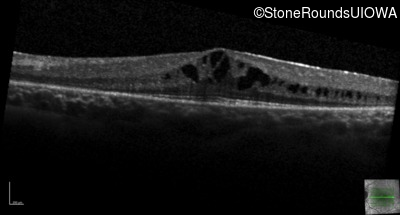

Age at visit: 7 years

OD OS

This 7 year old girl has had very poor vision in dim light and slightly subnormal acuity her entire life.